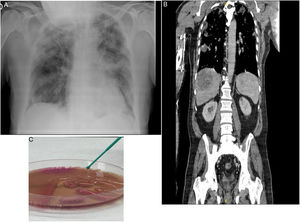

Our patient was a 70-year-old man from Algeria, resident in Spain, who had not recently traveled, former smoker of 16 pack-years, type 2 diabetic, with chronic ischemic heart disease and no history of respiratory disease, receiving atenolol, ramipril and metformin. He attended the emergency department due to a 3-day history of fever, nausea, and right pleuritic pain. Examination revealed: fairly poor general condition; tachypnea at 22 breaths/min; O2 delivered by nasal cannulae at 4 l/min; SaO2 95%; blood pressure 100/50 mmHg; heart rate 85 bpm; temperature of 39 °C; pulmonary auscultation: crackles reaching the bilateral mid-lung fields. A chest X-ray was performed in which peripheral infiltrates were observed in both hemithoraces, consistent with bronchopneumonia Fig. 1A).

Additional emergency tests showed arterial blood gases (FiO2 0.21); pH 7.44, PaCO2 31 mmHg, PaO2 53 mmHg, HCO3 20.9 mmol/l, PaO2/FiO2 252. Blood tests showed leukocytes 8,310/ml, neutrophils 77%, lymphocytes 8.1%; RBCs 4,100,000/ml; hemoglobin 12.2 g/dl; hematocrit 33%; platelets 119,000/ml; Quick 68%; D-dimer 1,772 ng/ml, glucose 280 mg/dl, urea 42 mg/dl; creatinine 1.46 mg/dl; albumin 2.40 g/dl; sodium 130 mmol/l; potassium 3.50 mmol/l; ALT 143 U/l; LDH 281 U/l; C-reactive protein > 25 mg/dl. Urine sediment was normal. PCR for SARS CoV-2 was negative. At 48 h, blood cultures showed growth of multisensitive K. pneumoniae. Urine culture and antigenuria for Legionella and pneumococci were negative. At 24 h, the patient presented hypotension, increased tachypnea, temperature of 38 °C and radiological deterioration, with patchy infiltrates progressing bilaterally. Thoracoabdominal CT showed bilateral pleural effusion associated with multiple nodular alveolar infiltrates, crazy-paving pattern in both apices, and anterior segments of both upper lobes showed filling defects in bilateral lobar pulmonary arteries. There were 2 focal heterogeneous lesions consistent with liver abscesses, measuring 8.8 × 6.5 cm and 2 cm, bilateral peripheral acute pulmonary embolism, with no signs of right overload, and septic emboli (Fig. 1B). Given his poor progress, he was admitted to the intensive care unit (ICU). Ultrasound cardioscopy showed LVEF 60% with no right heart dilation. Deep vein thrombosis of the lower extremities was ruled out by Doppler ultrasound.

Percutaneous puncture and drainage of the liver abscess were performed, and the culture grew multisensitive, ampicillin-resistant K. pneumoniae capsular serotype K1, hypermucoviscosity phenotype (Fig. 1C). In serologies for Epstein–Barr virus, cytomegalovirus, and herpes simplex virus 1 and 2 we obtained IgM negative and IgG positive antibodies, all consistent with recent infection and ruling out acute viremia. Serologies for syphilis, HIV, HBV, and HCV were negative.